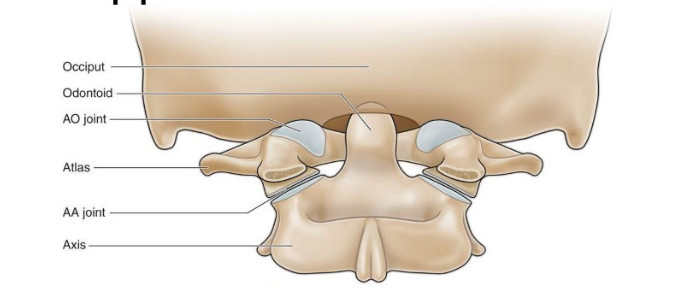

Label from top to bottom

occiput (back of the head)

odontoid

AO joint

atlas

AA joint

axis

Where does C1/atlas articulate

-articulates with the base of the skull (occiput) via the atlanto-occipital joint (nodding/ up and down movement)

-articulates with axis/C2 via the atlanto-axial joint for side-to-side rotation)

What type of joints are AO joints

condyloid joints (type of synovial joint)

Features of AO joints

classified as synovial joints with capsules

very mobile with primarily ligamentous stabilisation

facilitate occipital flexion and extension on the atlas/C1

What type of joints are the AA joint

pivot joint

How many AA joints are there

3

What type of movement do the AA joints allow and how

rotation / side to side movement of the head

there is a pivot joint between the odontoid process of the axis and ring formed by the anterior arch and the transverse ligament of the atlas